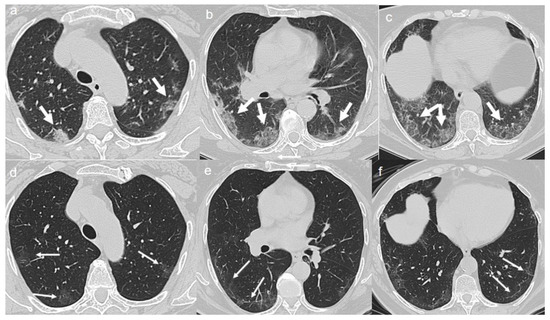

On admission, chest CT showed a diffuse “crazy paving pattern” peripherally located in the upper and lower lobes (Figure 3a–c).

A CT at 4 months from the onset of symptoms revealed the bilateral persistence of a mixed pattern characterized by GGOs and fibrous streaks (Figure 3d–f).

Figure 3. (ac) CT shows a “crazy paving pattern” peripherally located in upper and lower lobes (arrows). (df) CT after 4 months from the onset of symptoms shows bilateral persistence of mixed pattern of GGOs (thin arrows in d) and fibrous streaks (thin arrows in e,f).